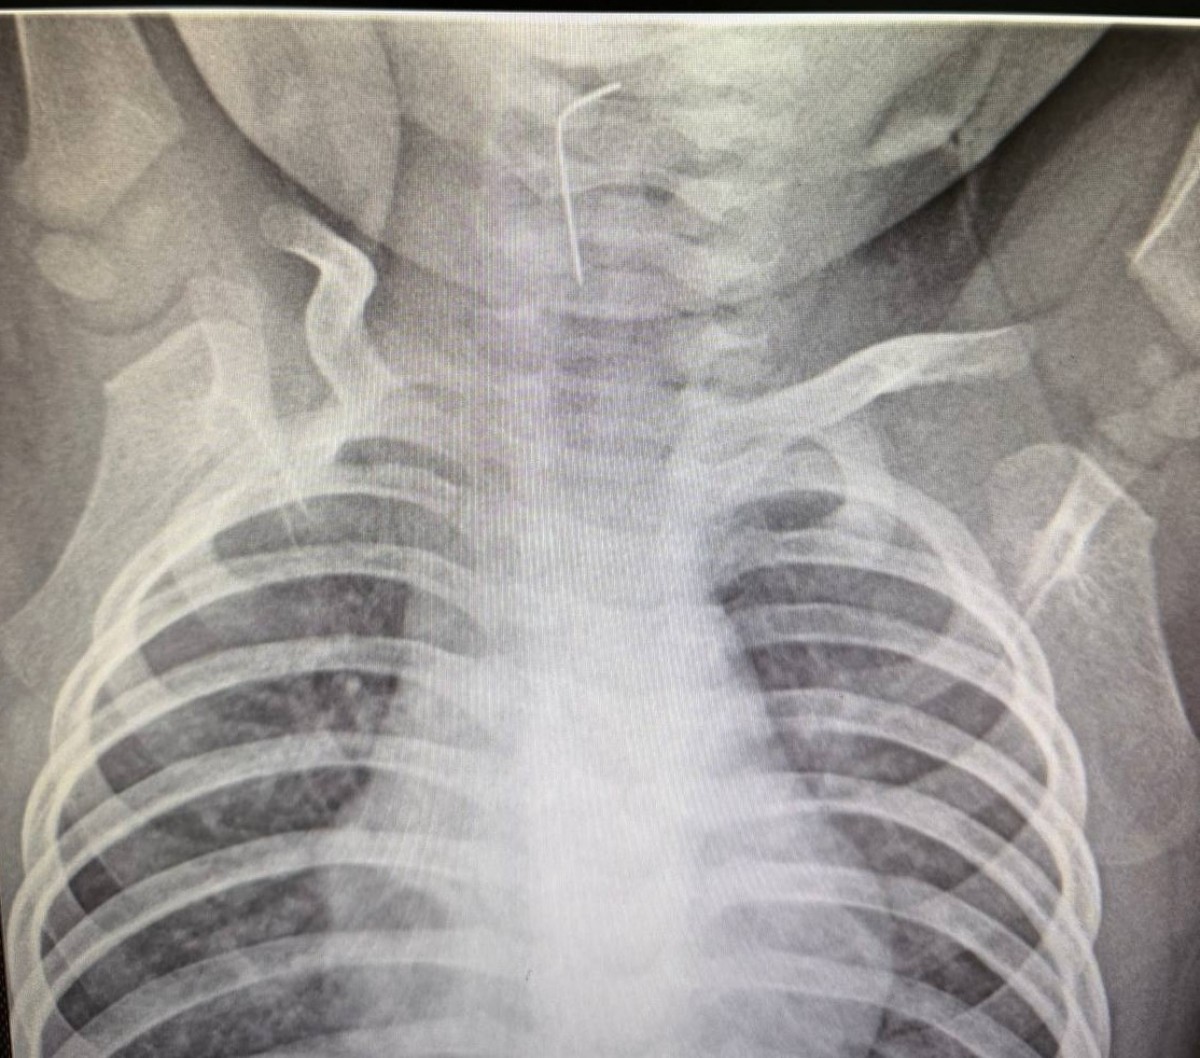

Түркістан облысында 9 айлық бала ине жұтып қойған

Түркістан облыстық балалар ауруханасына жедел жәрдем қызметі арқылы 9 айлық сәби шұғыл түрде жеткізілді, деп хабарлайды kznews.kz Түркістан облысының әкімшілігіне сілтеме жасап.

Белгілі болғандай, бала ине жұтып қойған. Дәрігерлер бірден рентгендік тексеру жүргізіп, эндоскопиялық әдіс қолданған. Нәтижесінде бөгде заттың нақты орны анықталып, өңешке тұрып қалған ине сәтті түрде алынды.

Мамандардың жедел әрі кәсіби көмегінің арқасында ықтимал асқынулар алдын алынды.

Қазіргі таңда баланың жағдайы тұрақты. Бақылау кезеңінен кейін сәби үйіне шығарылған.